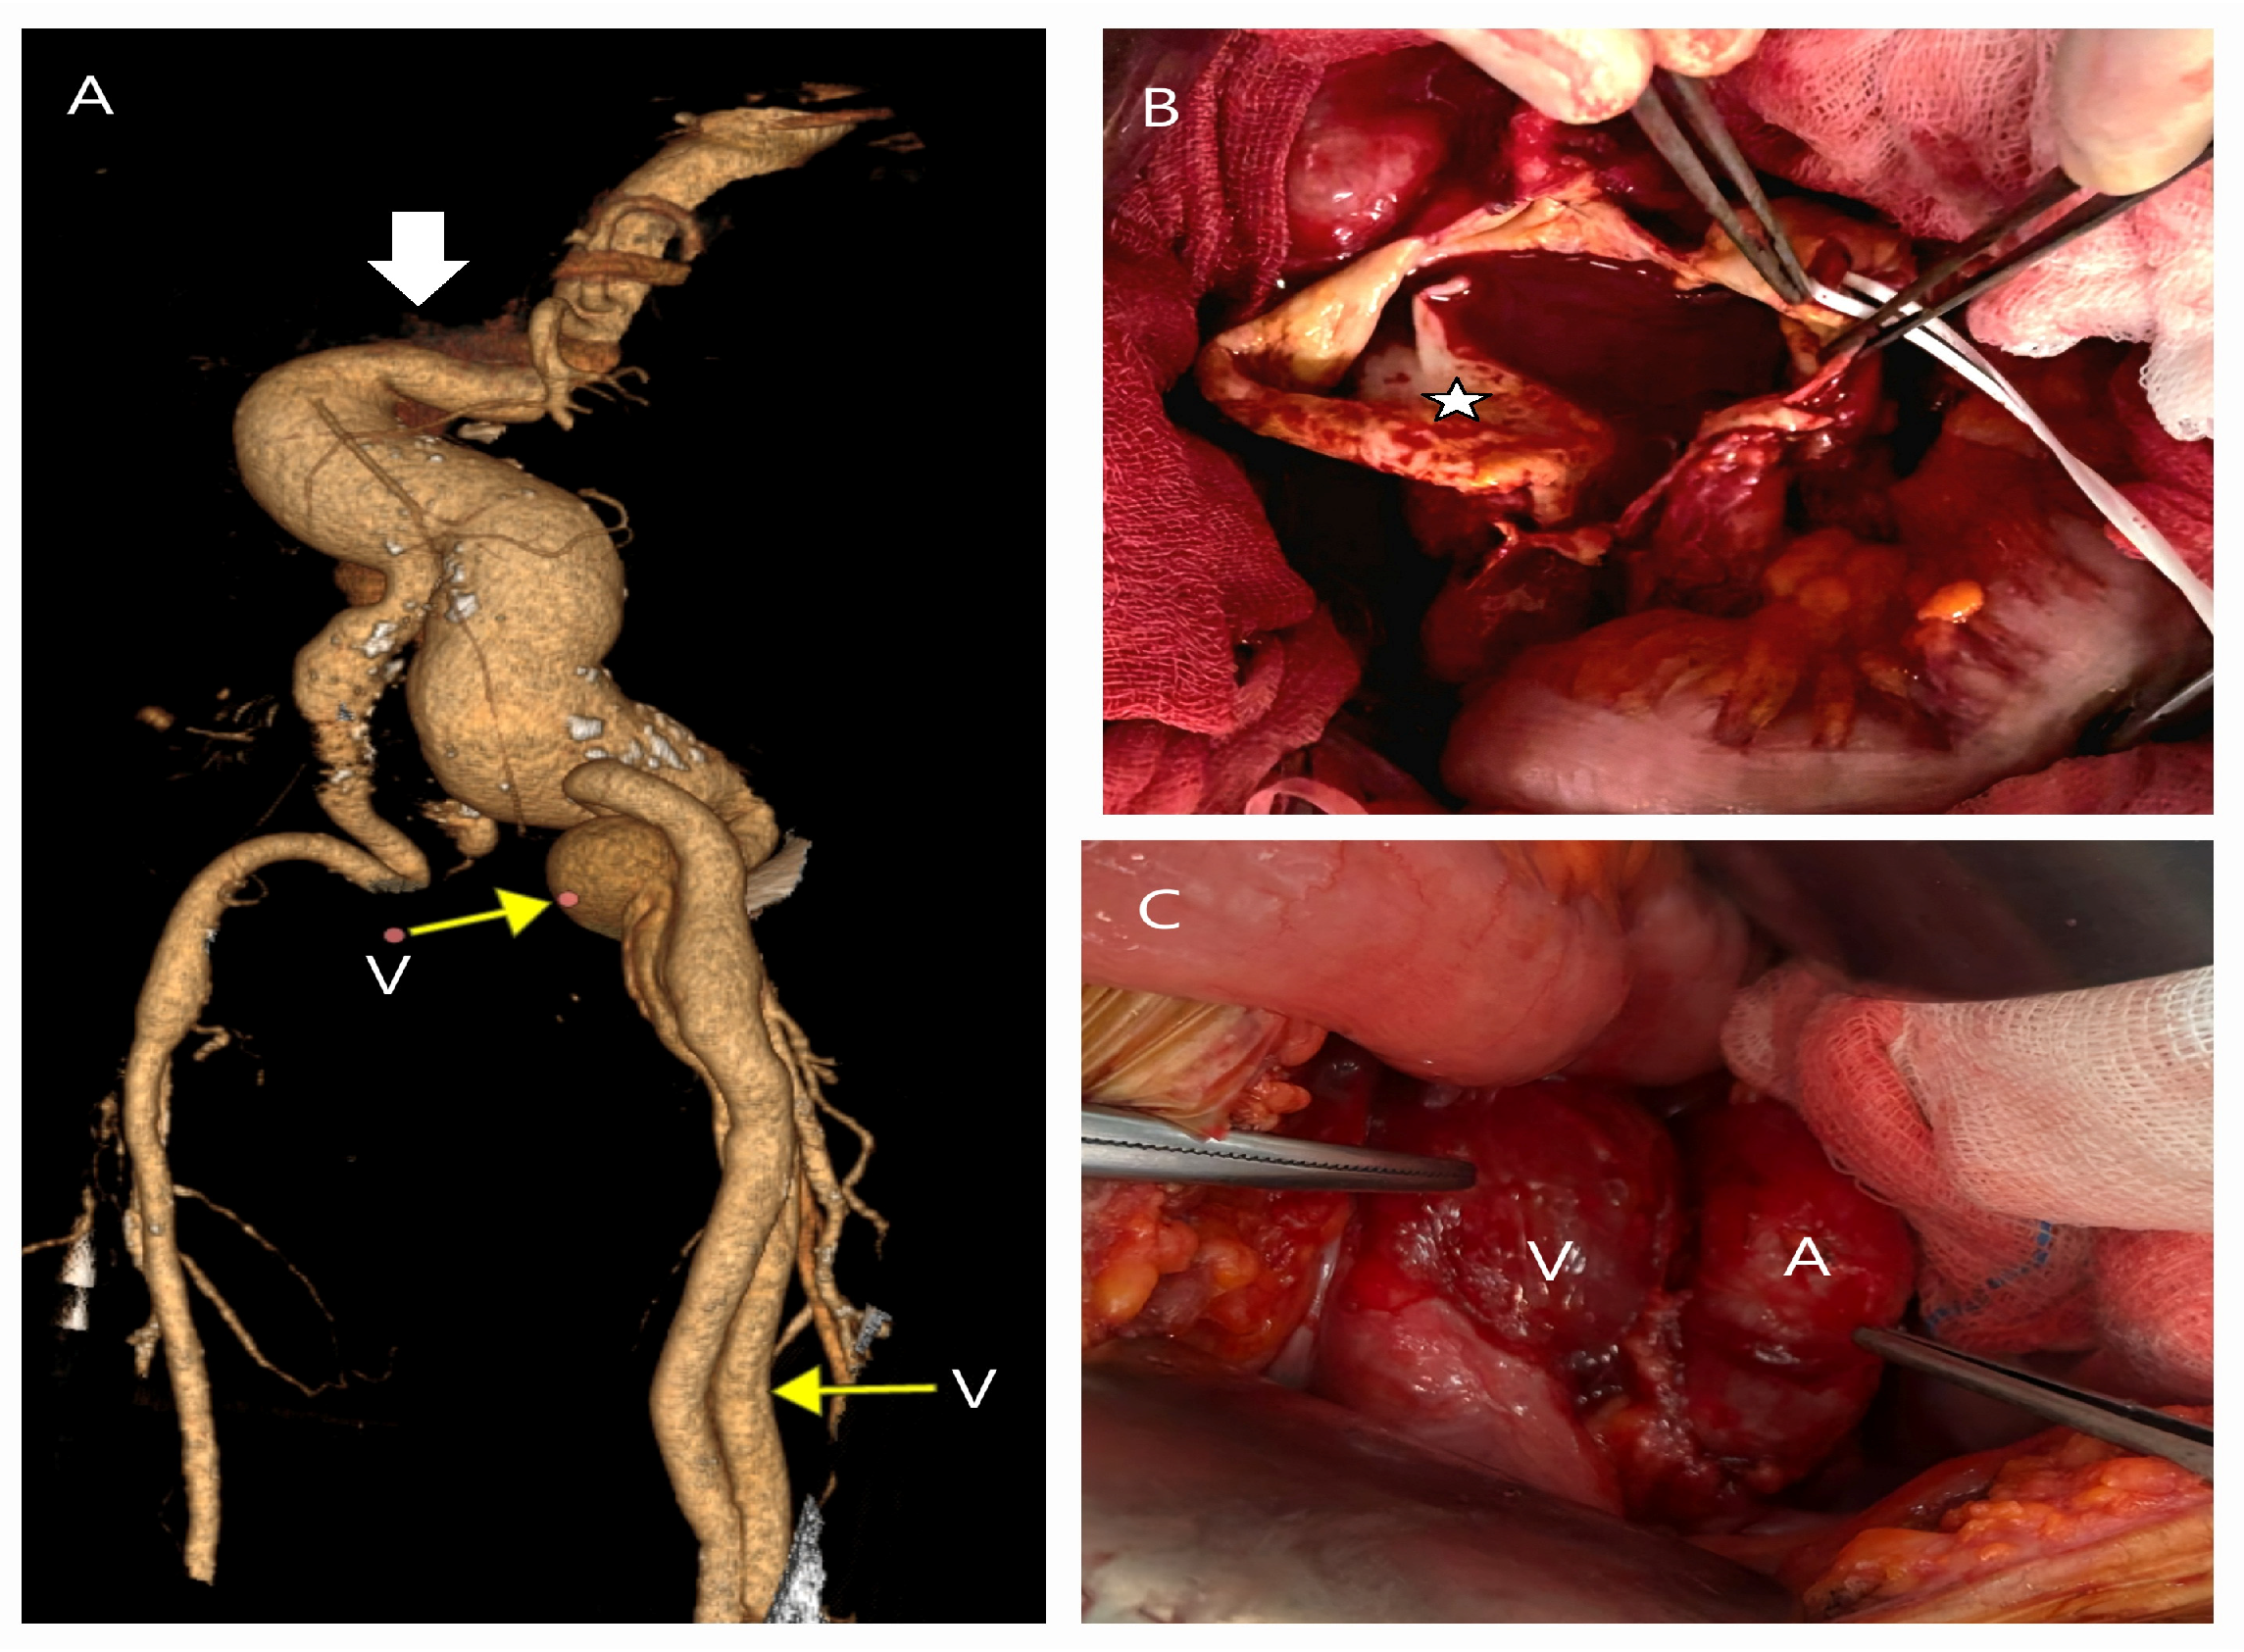

5.2. Conversion to Open Surgery